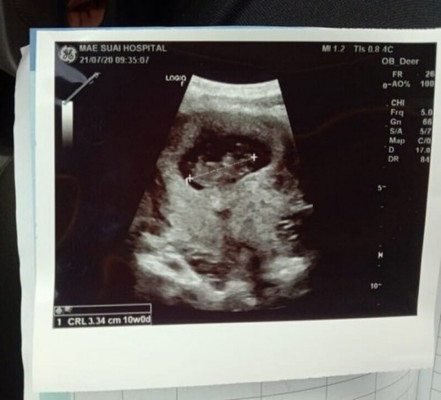

ซาวด์มาวันนี้ค่ะ21/7/63 9w3d แต่ตัวเจ้าน้อยมีขนาดเท่า10w เป็นครั้งแรกที่ได้เห็นผ่านจอแต่ตื่นเต้นดีใจมาก ชอบหยิบใบซาวด์มาดูแล้วดูอีก ดีใจมากค่ะ